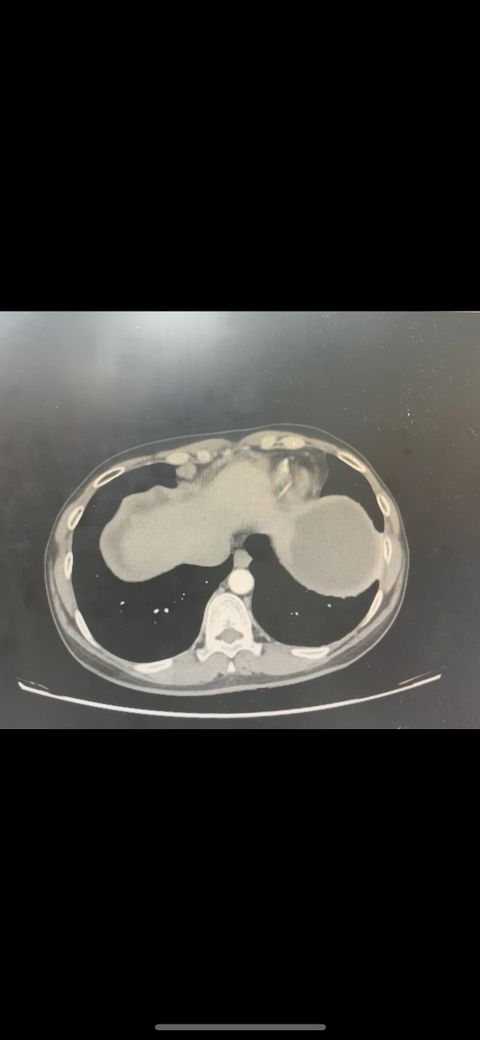

복부 ct 영상 판독부탁드립니다.!

결과는 3일 후 볼 예정인데 우선 영상만 받은 상태이고 너무 궁금한데 영상가지고 판독을 못해서요,,

이 사진가지고 확인할 수 있을까요 ?